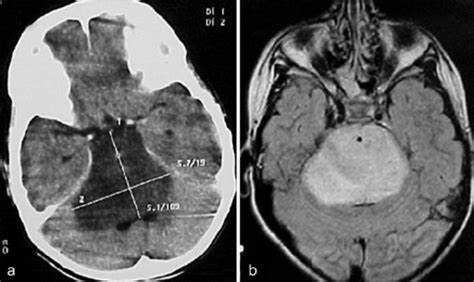

直到1980年代,计算机断层扫描一直在评估脑干肿瘤患者中发挥作用,后其迅速被MRI取代,MRI成为主要的诊断工具。MRI对肿瘤的生长部位、范围和方向以及其他形态学特征(例如病变是局灶性、弥散性、实体性还是囊性性)给出了清晰的实际影像。因此,MRI允许临床医生建立脑干胶质瘤的更精确特征,并确定肿瘤的位置和脑干胶质瘤的生物学行为。

通常,弥散性低级胶质瘤在髓质(60%)和脑桥(30%)中表现为浸润性和界限分明的肿瘤。在T1加权MRI上图像为等强度或低等,在T2加权或液衰减倒置恢复(FLAIR)图像上为高强度。它们通常缺乏对比度增强。有时可以观察到沿小脑中部渗入小脑或直接渗入中脑。成人恶性脑干胶质瘤表现为增强对比的肿瘤,伴有瘤周水肿。MRI上的环状增强提示病灶内坏死。通常需要进行鉴别诊断,因为其他病理实体类似于这种类型的脑干胶质瘤,具有类似的对比增强作用(淋巴瘤、炎性疾病、脓肿、转移、脱髓鞘疾病、室管膜瘤、血管母细胞瘤和梗塞)。局灶性顶盖脑干胶质瘤是在顶板或导水管周围区域的明确病变。

这些肿瘤在T1加权图像上表现为等强度或低强度,在T2加权图像上表现为高强度。通常不存在对比度增强。通常,它们在形态上保持稳定多年。外生性脑干胶质瘤通常表现为源于四脑室底部的肿块。在造影剂增强的情况下,此类病变可误诊为室间隔膜瘤或脉络丛乳头状瘤。通常不存在对比度增强。通常,它们在形态上保持稳定多年。外生性脑干胶质瘤通常表现为源于四脑室底部的肿块。